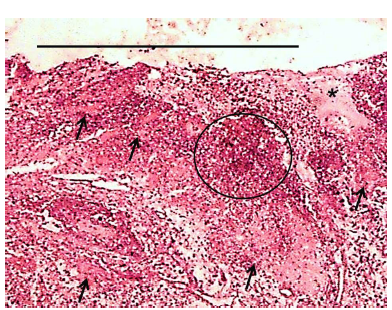

En todas las biopsias de tejido tumoral teñidas con la coloración de H-E, se observaron características histopatológicas similares entre ellas, las cuales consistieron en la presencia una dermatitis piogranulomatosa activa con áreas de necrosis multifocal, en algunos casos se observaron larvas del parásito y múltiples fenómenos de Splendore-Hoeppli (SH), la epidermis se observó ulcerada con una fina capa de restos celulares necróticos mezclados con neutrófilos, la dermis se observó marcadamente congestiva y edematosa (FIG. 3), siendo altamente compatible con el cuadro de habronemosis, ya que las tinciones especiales de PAS y Grocott fueron negativas para hongos.

Los hallazgos histopatológicos con la tinción de H-E, corresponden con los reportados por Amininajafi y col. [2]; Down y col. [12], Pugh y col. [27] y Schuster y col. [28] en las que se describe una dermatitis piogranulomatosa, con diferentes áreas de necrosis y gran número de eosinófilos en la periferia. Maciel y col. [17] y Marcolongo-Pereira y col. [18] destacan la importancia de la histopatología, debido a la similitud entre la localización de las lesiones, el tiempo de ocurrencia y las características macroscópicas entre habronemosis y pythiosis.